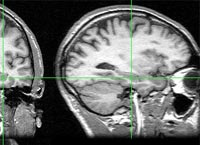

Enquanto isso era feito, seus cérebros eram examinados por ressonância

magnética, de modo a registrar a atividade cerebral por meio

da medição de alterações no fluxo sanguíneo.

Por meio da análise de imagens da atividade cerebral,

programa desenvolvido por cientistas britânicos acerta em quais

de três filmes, exibidos anteriormente, voluntários estavam

pensando (imagem: Wikipedia)